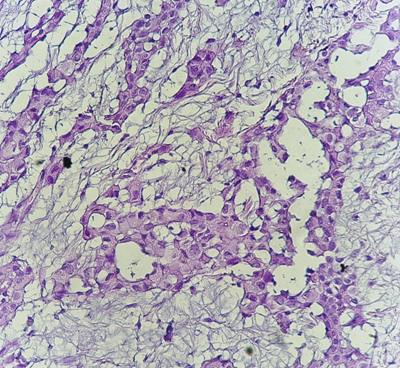

The diagnosis of MPM was confirmed by pleural puncture biopsy in a single patient, and in 7 patients (87.5%), the biopsy was performed under thoracoscopy. The pathological study was in favor of malignant pleural mesothelioma with an undetermined histological subtype in 7 patients (Figures 1–3), the epithelioid form was found in a single patient. Pleural fluid cytology was not been done.

Figure 1 Histological study: HES*200: Carcinomatous proliferation arranged in spans and tubes (pathology department of CHU Hassan II in Fez).

Figure 2 Histological study: HES*400: the tumor cells are large in size with large nuclei. (Pathology department of CHU Hassan II of Fez).